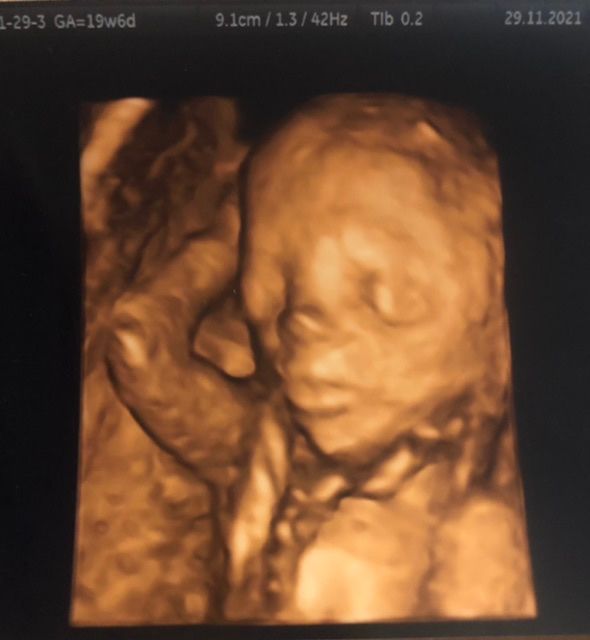

2 скрининг💓

Смешная какая) моя тоже лежала так забавно руки за головой, на расслабоне на чилле так сказать))) Скажу , что очень быстро идет время !! и вот уже скоро на 3 узи) жду не дождусь, схожу с ума уже)) Изображение

Поздрааляю вас ❤ все детки это чудо, особенно свое) но эти 3д узи меня пугают 🤣🤣 нашего на 1м скрининге зафоткали и это какой то воландеморт а не дите 🤣🤣 да уж, я по своему умиляюсь)

Светлана , я не делаю 3д узи,они меня пугают 🙈🤣

Мария, вот вот, ну это ж капец 🤣🤣 я конечно на узи умиляюсь когда включают, но я налеюсь что малыш будет похож на человека, а не чужого 🤣🤣🤣

Светлана , мне тоже все родственники сказали « какая красавица!»😳 я почему то ничего красивого не вижу пока😂

Lina Love, вот точно 😁😁 но профиль красивы на чб фото)) вот их и прошу печатаиь)

Irina, примерно 154мм) на 2 скрининге уже точный размер в длину не пишут, ну у меня так по крайней мере)